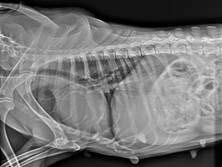

影像学表现为溶骨性膨胀性病变,伴增生性骨膜反应,边缘不规则,骨膜反应呈点状至柱状(图3)。肿瘤起始于鼻孔末端延伸至眼眶区域,与正常骨组织的过渡区界限不清。额骨、鼻骨及上颌骨可见明显破坏,提示为侵袭性骨病变。

图3. X线片示溶骨性膨胀性病变,伴增生性骨膜反应,边缘不规则,骨膜反应呈点状至柱状。

本例报告了一例12岁母犬,其前鼻骨区域出现一巨大组织细胞瘤,直径约10厘米,病程进展迅速。该病例在临床、影像学及病理学上均表现出一定复杂性,尤其在老年犬中较为罕见,增加了诊断难度。初步影像学检查显示该肿瘤伴随明显的骨破坏和骨膜反应,提示为侵袭性病变,因此需与多发性骨髓瘤、骨肉瘤、鳞状细胞癌等恶性肿瘤鉴别。